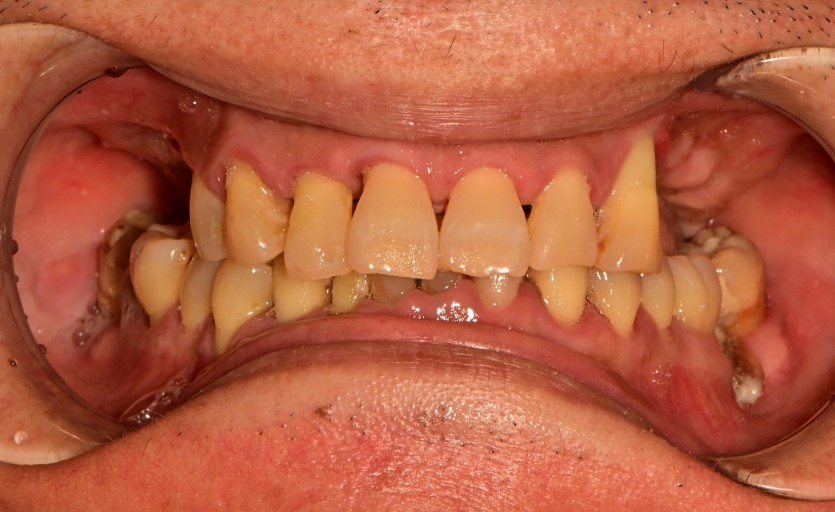

전체 임플란트 증례입니다.

18개의 임플란트로 완성하였습니다